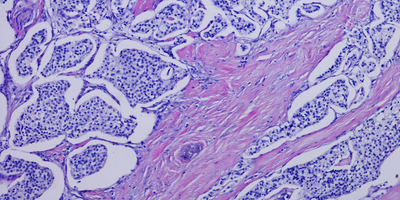

Researchers reported findings for how two subtypes of pancreatic cancer respond to treatments differently